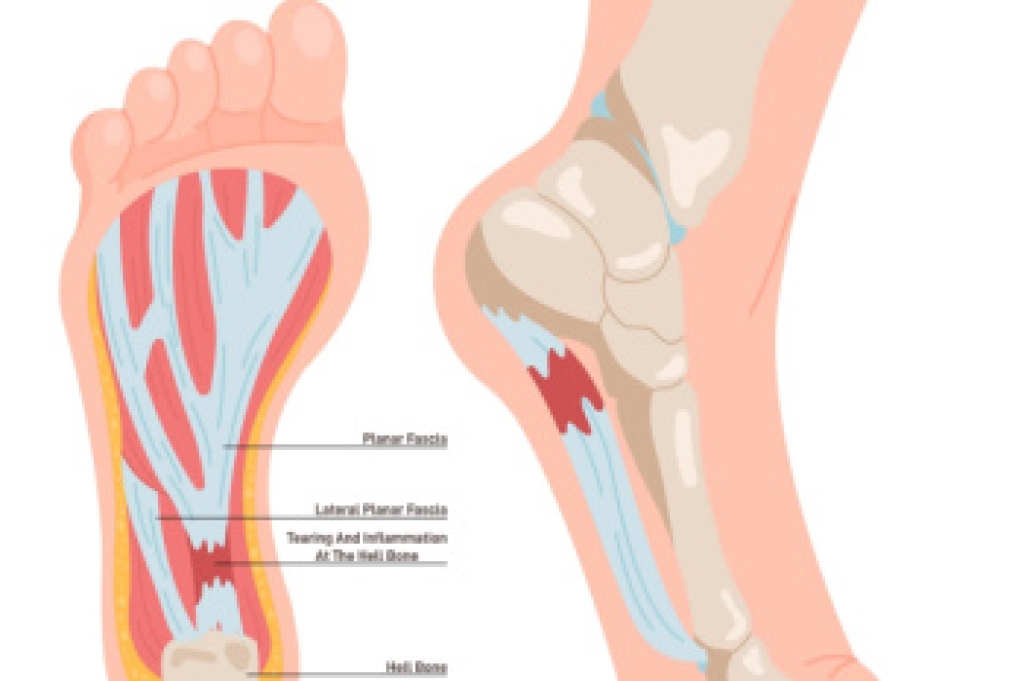

What Is Plantar Fasciitis?

Plantar fasciitis is one of the most common causes of heel pain. The plantar fascia is a ligament that connects your heel to the front of your foot. When this ligament becomes inflamed, plantar fasciitis is the result. If you have plantar fasciitis you will have a stabbing pain that usually occurs with your first steps in the morning. As the day progresses and you walk around more, this pain will start to disappear, but it will return after long periods of standing or sitting.